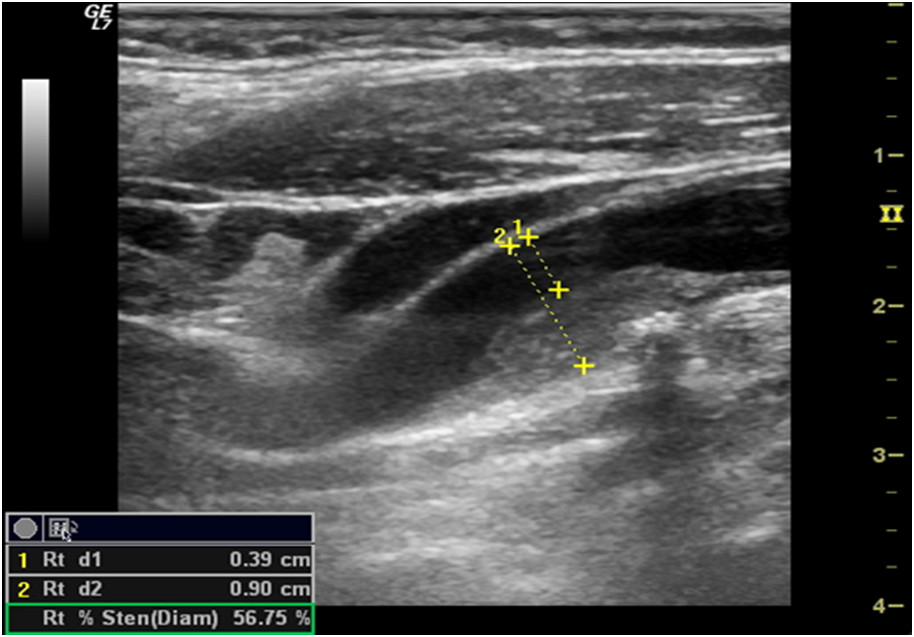

Podczas badania ultrasonograficznego tętnic szyjnych stwierdzono obecność miernie uwapnionych blaszek miażdżycowych w odcinku bliższym tętnicy szyjnej wewnętrznej (ICA). Na jednym przekroju poprzecznym ICA zmierzono średnicę naczynia i kanału drożnego (patrz rycina). Uzyskany wynik jest: